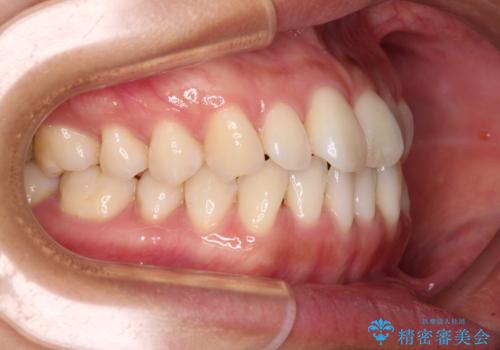

- 前歯のデコボコで前方に出ていることを気にして来院された患者様です。

上顎前歯が捻れて前方に飛び出しており、下顎前歯もそれに沿うようにデコボコとなっていました。

IPR(歯と歯の間を削る処置)によりスペースを獲得して上下顎前歯のデコボコを改善し、飛び出している前歯が引っ込むように設定し、インビザラインにて矯正治療を行うこととしました。

装着時間を守ってくださったので、予定通りの期間で終えることができました。インビザライン特有の、奥歯の咬み合わせの問題もなく、しっかりと歯列を改善することができました。